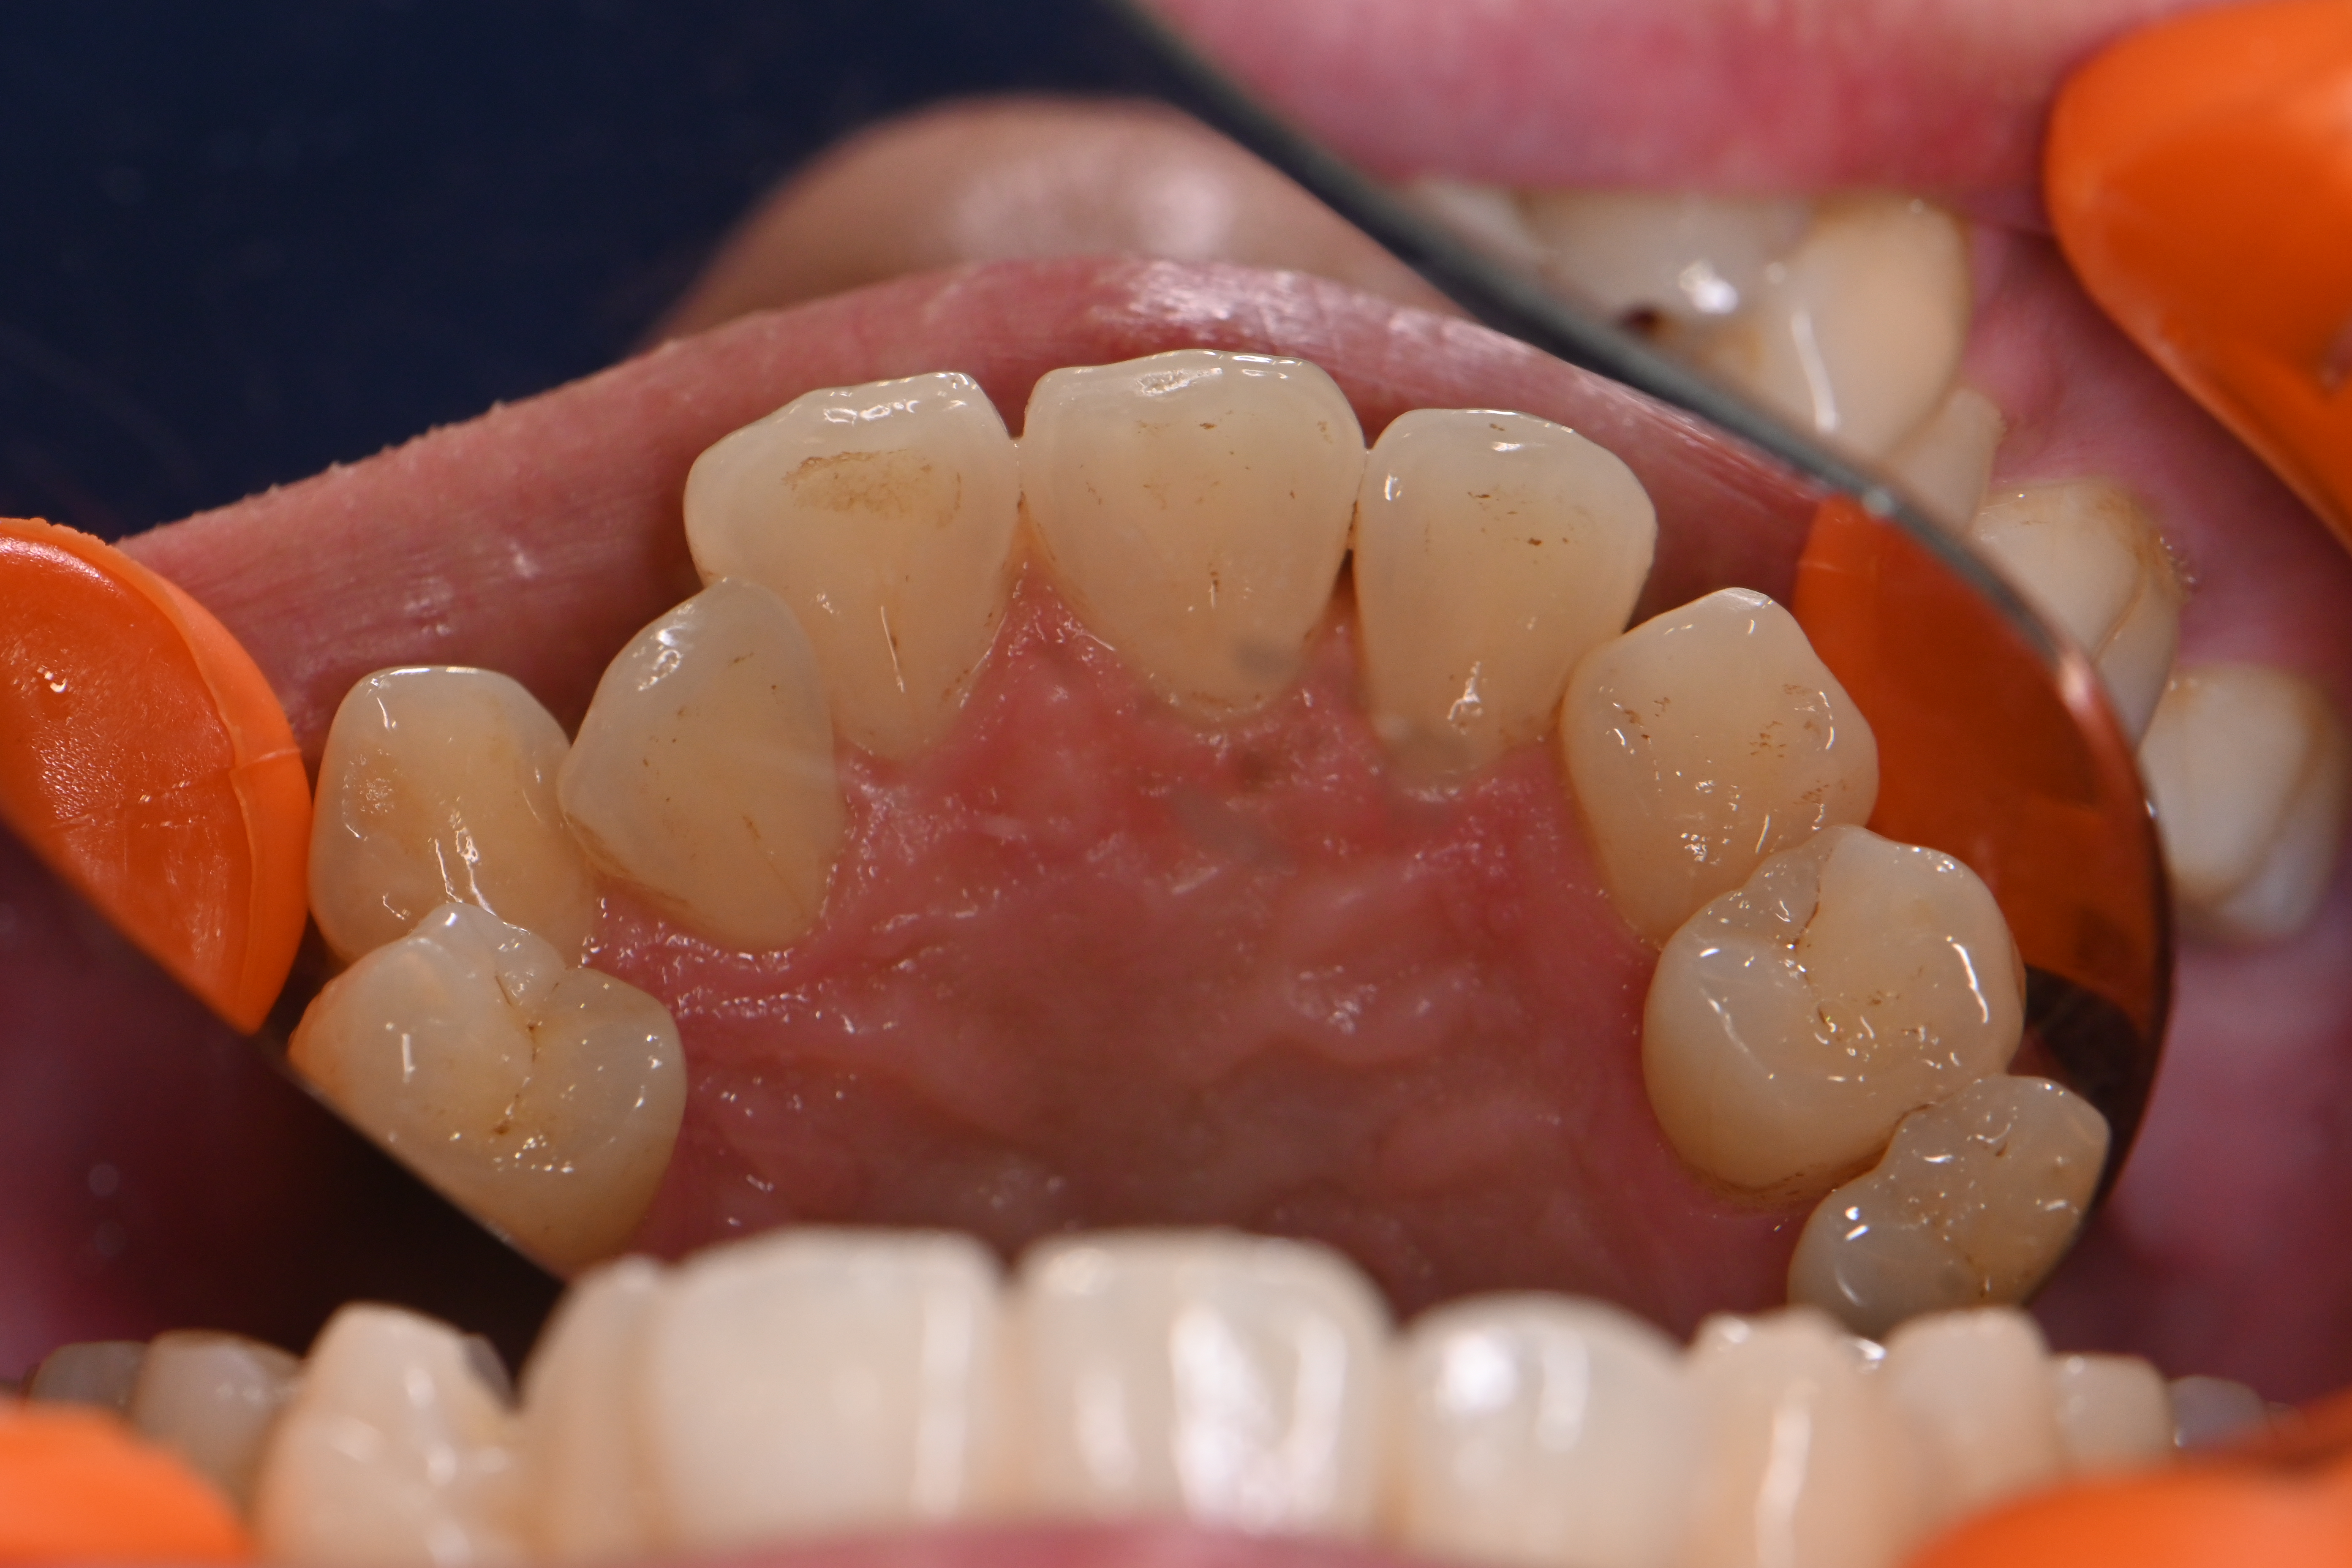

今回は全体的に着色が気になる方の症例です。

他の歯医者さんで以前からエアフローで着色を除去されてきた患者様ですが、前回してから半年期間が空いてしまったら再度着色が目立つようになったのこと💦

細かい着色をエアフローでしっかり除去して、仕上げにリナメル(歯の細かい傷を埋めてくれる)を塗布しました✨

場所によっては分厚い磨き残しがあり、そこに着色していた箇所もあったため歯磨き指導も一緒にさせていただきました。